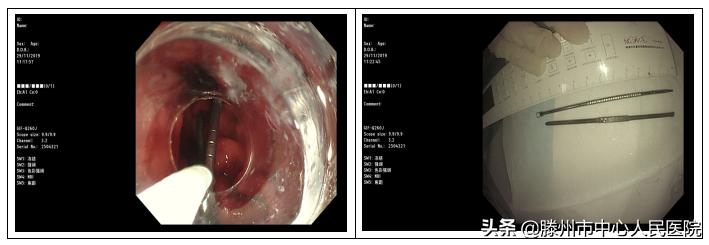

钢针